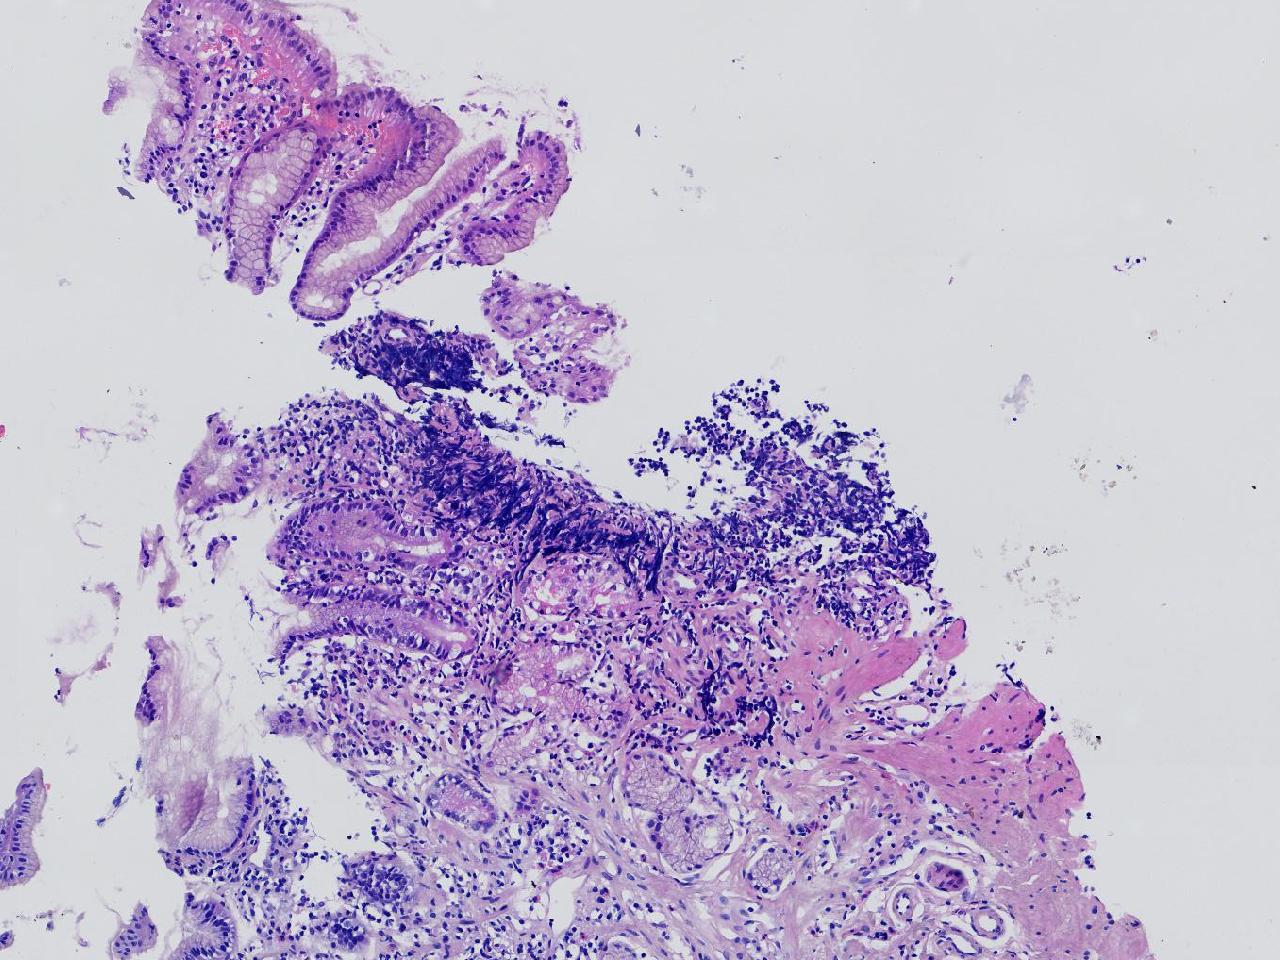

1.间质内淋巴组织有问题吗? 2.有没有低瘤变?

一般病史男,65岁,胃镜活检,胃窦粘膜红白相间,花斑样改变,大弯侧粘膜变薄,血管透见,可见多发片状充血糜烂灶及点状褐色物覆着,活检2块送检,质软弹性可。

标本名称胃窦活检

大体所见灰白色不整形软组织2块,直径均0.2厘米。

慢性萎缩性胃炎伴肠化,固有层淋巴细胞聚集

萎缩性炎,伴有肠化,淋巴组织挤压变形,感觉没有太大的问题。

炎性,无瘤变。